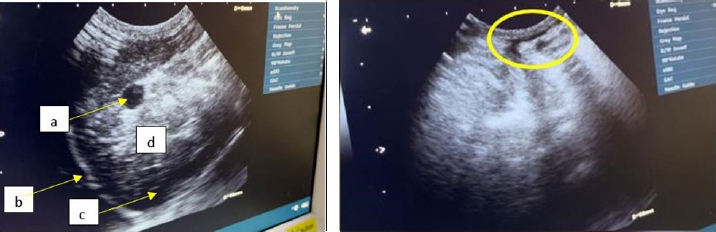

USG interpretation

The findings of USG performed in the dorsal recumbent position on the thoracic and abdominal regions revealed the existence of fluid accumulation in the peritoneal cavity (Fig. 4).

The abdominal cavity examination conducted through USG revealed certain structures appearing anechoic on the sonogram, indicating the presence of ascitic fluid in the abdominal cavity (Prajapati et al., 2022).

The findings from the ultrasound assessment revealed that the cardiac organ exhibited a normal structure (Fig. 5). The inability of researchers to utilize color flow Doppler imaging, a modality that permits direct visualization of blood flow velocity within the heart and related blood vessels, and consequent description of turbulent blood flow patterns, has precluded observation of blood flow in the heart of the Hiro cat.

Fig. 4. The abdominal region of Hiro, a feline specimen, displays the presence of ascites as evidenced by medical imaging using USG.

Fig. 5. Ultrasound results of cat Hiro’s heart structure, (left: long axis, right: short axis) right parasternal view position.